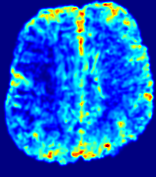

Slice #1Slice #2Slice #3Slice #4Slice #5Slice #6𝐕gt2subscriptnormsuperscript𝐕gt2\|{\bf{V}}^{\text{gt}}\|_{2}Refer to captionRefer to captionRefer to captionRefer to captionRefer to captionRefer to caption(a)Refer to captionRefer to captionRefer to captionRefer to captionRefer to captionRefer to caption(b)Refer to captionRefer to captionRefer to captionRefer to captionRefer to captionRefer to caption(c)Refer to captionRefer to captionRefer to captionRefer to captionRefer to captionRefer to caption(d)Refer to captionRefer to captionRefer to captionRefer to captionRefer to captionRefer to caption(e)Refer to captionRefer to captionRefer to captionRefer to captionRefer to captionRefer to caption(f)Refer to captionRefer to captionRefer to captionRefer to captionRefer to captionRefer to captionRefer to caption000.30.30.30.60.60.60.90.90.91.21.21.21.51.51.5(mm/s)𝑚𝑚𝑠(mm/s)

Figure 12: PIANO effectiveness and robustness testing: advection imaging via advection. Top row shows the ground truth 𝐕gt2subscriptnormsuperscript𝐕gt2\|{\bf{V}}^{\text{gt}}\|_{2} used for simulating pure advection. (a)-(f) refer to the results for 𝐕2subscriptnorm𝐕2\|{\bf{V}}\|_{2} estimated by PIANO, with simulated advection imaging series where Rician noise at levels 0%, 2%, 4%, 6%, 8%, 10% was added respectively.

We further simulate noisy concentrations by adding Rician noise [24] with variances equalling 2%, 4%, 6%, 8%, 10% of the originally simulated concentrations {Cti}superscript𝐶subscript𝑡𝑖\{C^{t_{i}}\}. We then test how well PIANO can estimate the underlying velocity field via Eq. 15 with the same model settings (except without estimating the diffusion) as in Sec. 3 given the original and the noisy concentration time-series. Fig. 12 shows the estimated 𝐕est2subscriptnormsuperscript𝐕est2\|{\bf{V}}^{\text{est}}\|_{2} for one patient. Fig. 11 (a) shows the summarized estimation results for all 43 patients. PIANO almost perfectly captures the underlying velocity field, and maintains excellent performance even when estimating from concentrations with varying noise levels.